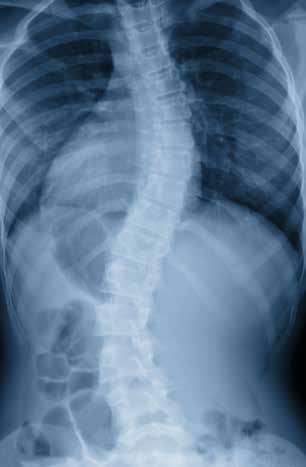

DR. DANIEL KRAUS COMBINES ADVANCED BIOMECHANICS WITH PRECISION SPINAL CARE

Dr. Daniel Kraus, DC, owner and clinical director of Bethesda Spine & Posture in Bethesda Row, is not your typical chiropractor. Practicing since 1997, Dr. Kraus has developed one of the region’s most advanced non-surgical spinal rehabilitation program, an approach he describes as “a specialty within a specialty within a specialty.”

He is one of only a handful of chiropractors in Maryland who hold an Advanced Certification in Chiropractic BioPhysics® (CBP), the most researched and results-driven method for structural correction of the spine.

What truly sets his practice apart, however, is the integration of ScoliCare® protocols, including ScoliBrace® and ScoliBalance®—for the non-surgical management of scoliosis, kyphosis, and postural deformities. This unique combination of CBP structural correction and ScoliCare 3D bracing represents a comprehensive, evidence-based approach to restoring alignment, stability, and function.

Scoliosis and Spinal Deformity Expertise

Dr. Kraus specializes in the conservative treatment of adult and adolescent scoliosis, kyphosis, and spondylolisthesis— conditions that can cause pain, fatigue, and progressive spinal collapse. His goal, he explains, is simple but ambitious: “These are collapsing deformities of the spine— and our mission is to stop that collapse.”

At Bethesda Spine & Posture, patients receive individualized care plans that may include CBP corrective traction, posture-specific exercise, and custom ScoliBrace® 3D bracing. Each brace is designed using a patient’s X-rays, photos, and 3D iPad scans, ensuring an exact fit that promotes spinal elongation, midline alignment, and de-rotation.

“People are amazed at how much taller, straighter, and more balanced they feel almost immediately,” says Dr. Kraus. While adolescents may wear the brace up to 22 hours daily during growth phases, adults typically use it for 4–8 hours a day as part of a broader posture restoration plan.